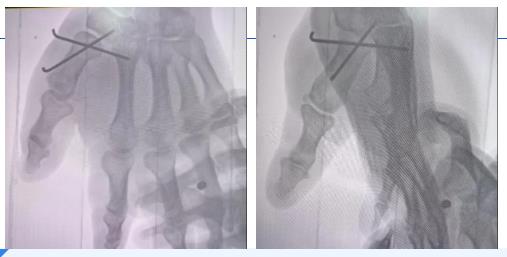

术中,青南支医医生王登峰采用“边操作边讲解”模式,手把手带领称多县人民医院外科医师进行手术。通过手术操作过程中手法复位时演示牵引、按压技巧,指导感受骨擦音与复位手感;克氏针内固定环节明确进针点与深度标准,石膏外固定阶段强调塑形对固定效果及血液循环的影响,强化其对手术流程的掌握。针对称多县人民医院外科医师对操作细节的积极提问,青南支医医生王登峰逐一解答,称多县外科医生表示在此次手术全过程的实践参与中收获颇丰。

术中C臂机透视检查显示骨折复位理想,脱位已纠正,内固定及外固定位置妥当,支医医生还就术后护理、注意事项、康复训练及并发症预防进行专项指导,保障患者恢复效果。